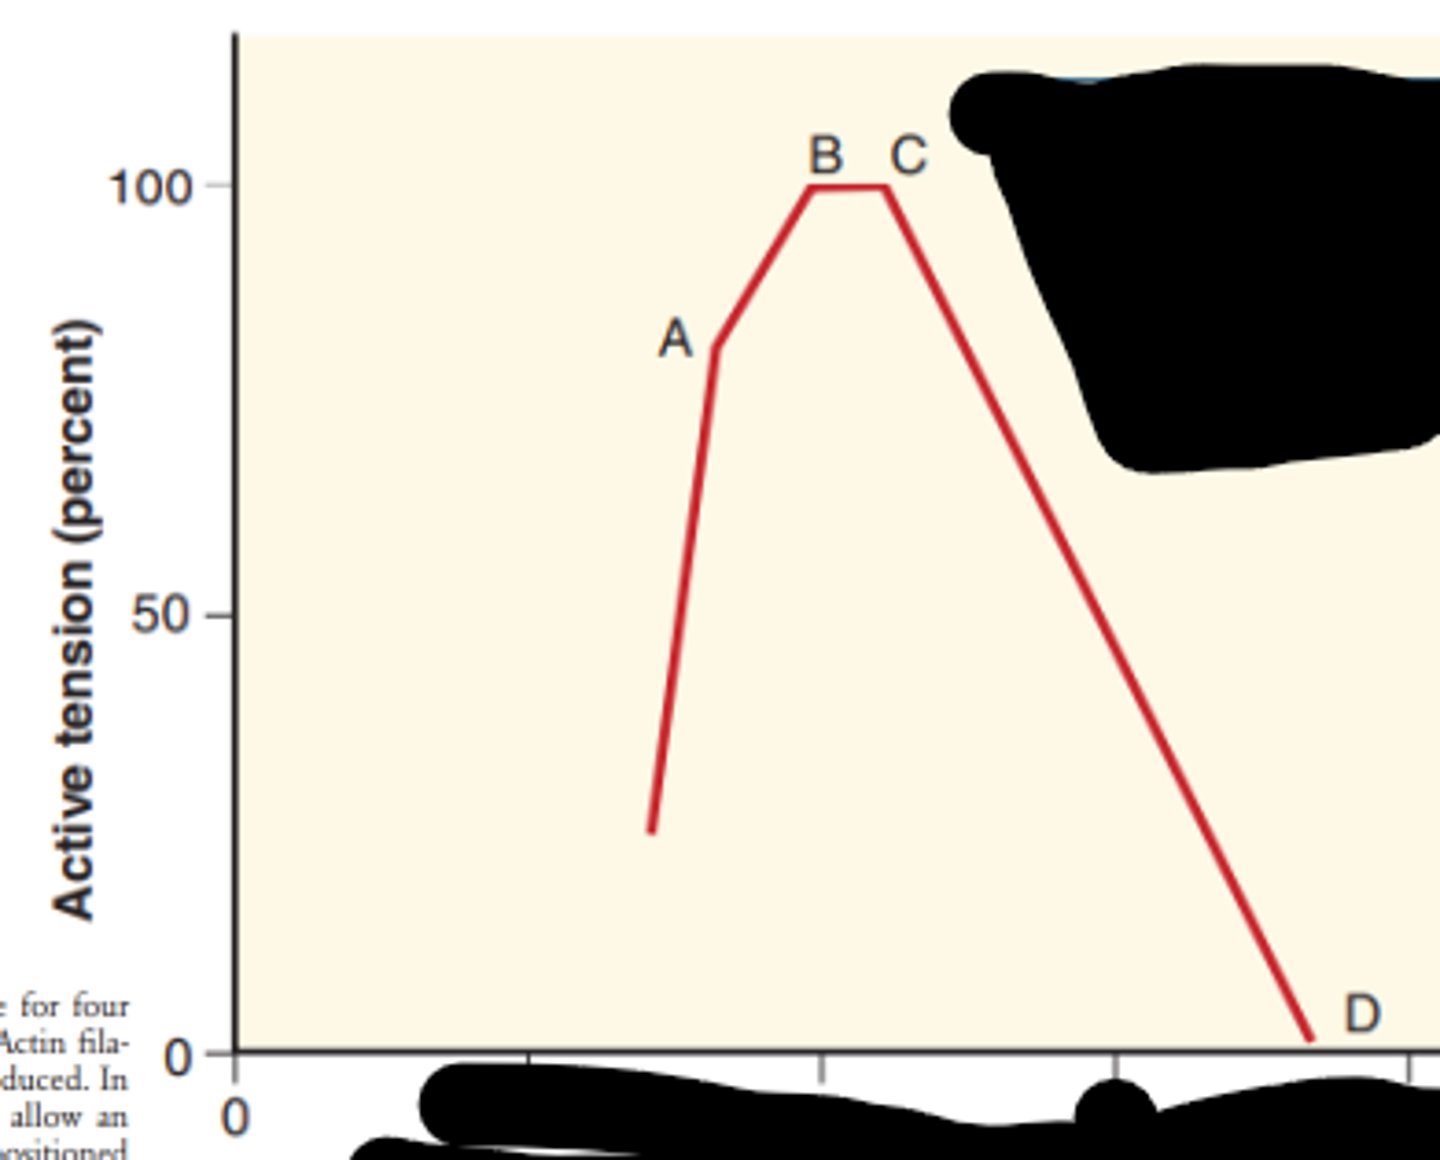

Where is the sarcomere the shortest length?

What does the red arrow represent?